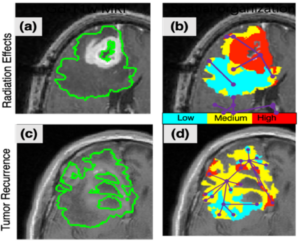

“We use spatial radiomaps (i.e. “virtual biopsy maps”), which act as a sort of GPS map. We take a simple MRI scan of the patient’s brain, and then apply the AI analysis to create the radiomap. From there, we look to see where the map says the tumor is, and we perform a biopsy to check for accuracy and see if that tissue is cancerous.”